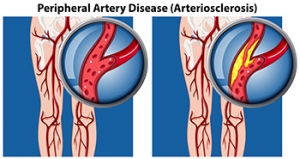

Causes and Diagnosis of Peripheral Artery Disease

Peripheral artery disease, or PAD, poses significant challenges for foot health, stemming from restricted blood flow to the lower extremities. This condition, often caused by atherosclerosis, involves the buildup of fatty deposits in the arteries, leading to narrowed or blocked blood vessels. The diminished blood supply to the feet can result in various symptoms, including pain, cramping, numbness, and weakness, particularly during physical activity. Left untreated, PAD can contribute to serious complications such as foot ulcers, infections, and delayed wound healing. Diagnosing PAD typically involves a comprehensive evaluation by a podiatrist. This process includes a thorough medical history review, assessment of risk factors such as smoking and diabetes, and a physical examination focused on evaluating circulation in the legs and feet. Specialized diagnostic tests, such as ankle-brachial index, or ABI measurement, Doppler ultrasound, and angiography, may also be employed to confirm the diagnosis and determine the extent of arterial blockages. If you are experiencing any of the foot symptoms mentioned above, it is suggested that you consult a podiatrist who can accurately diagnose and offer relief solutions for PAD.

Peripheral artery disease can pose a serious risk to your health. It can increase the risk of stroke and heart attack. If you have symptoms of peripheral artery disease, consult with Dr. James Kutchback from James Kutchback, DPM, ABLES, CWS-P. Our doctor will assess your condition and provide you with quality foot and ankle treatment.

Peripheral artery disease (PAD) is when arteries are constricted due to plaque (fatty deposits) build-up. This results in less blood flow to the legs and other extremities. The main cause of PAD is atherosclerosis, in which plaque builds up in the arteries.

Peripheral Artery Disease

Peripheral artery disease (PAD), or peripheral arterial disease, is a circulatory problem in which there is a reduction of blood flow to the limbs due to narrowed arteries. When peripheral artery disease develops, the extremities do not receive enough blood flow; this may cause symptoms to develop such as claudication, or leg pain when walking. The legs are the most common site of peripheral artery disease.

Claudication, or leg pain when walking, is one of several symptoms that can develop due to peripheral artery disease. Other symptoms caused by the disease include painful cramping in the hips, thighs, or calves after certain activities; leg numbness or weakness; coldness in the lower leg or foot; sores on the lower extremities that do not heal; hair loss on the lower extremities; and a missing or weak pulse in the lower extremities. In more severe cases, pain may even occur when the body is at rest or when lying down.

Peripheral artery disease is typically caused by atherosclerosis, a condition in which fatty deposits build up in the arterial walls and reduce blood flow. Smoking, diabetes, obesity, high blood pressure, and high cholesterol are some of the risk factors for peripheral artery disease.

Peripheral artery disease (PAD) can potentially lead to poor circulation in the lower extremities. PAD is a condition that causes the blood vessels and arteries to narrow. In a linked condition called atherosclerosis, the arteries stiffen up due to a buildup of plaque in the arteries and blood vessels. These two conditions can cause a decrease in the amount of blood that flows to your extremities, therefore resulting in pain.